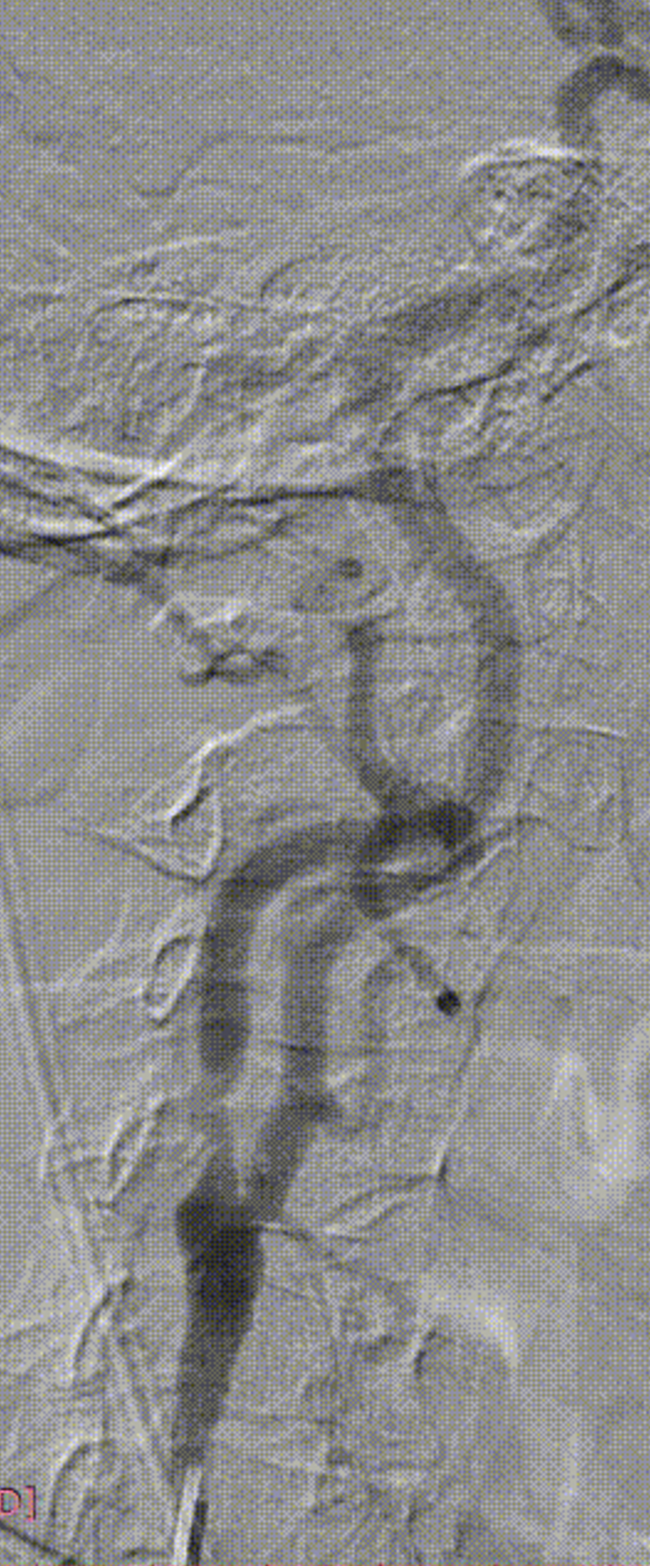

病例1:61岁男性,因双下肢间歇性跛行检查发现双侧颈动脉狭窄,冠脉情况严重,先行两次PCI,后行双侧CAS,先左后右,术后恢复良好。

左侧术前

左侧术后